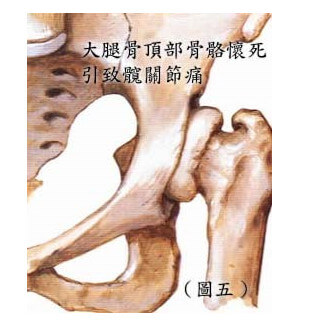

大腿骨頂部骨骼懷死

由於大腿骨頂部連接髖關節位,如大腿骨頂部骨骼懷死亦會產生髖關節痛楚。由於該處的血液循環不 足夠而引發頂部骨頭懷死。患者多數介乎於 25 至 45 歲,而 40% – 70% 患者最後亦會感到兩邊髖關節痛。 過量酒精及服用類固醇藥物都會嚴重影響這個病症。患者早期沒有痛的徵狀,只是覺得髖關節有些緊硬, 到後期當大腿骨頂部完全下陷,髖關節痛的情況近似退化性關節炎的徵狀。( 圖五 )